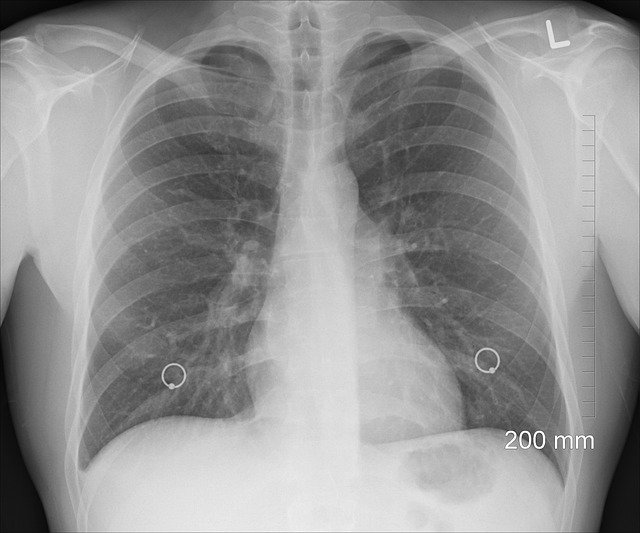

Болезнь органов дыхания

Легкие

Каковы распространенные профессиональные заболевания легких?

Возможен широкий спектр профессиональных заболеваний легких, но некоторые из них встречаются чаще других. К ним относятся:

• Профессиональная астма

• Черные легкие (пневмокониоз)

• Силикоз

• Асбестоз

• Мезотелиома